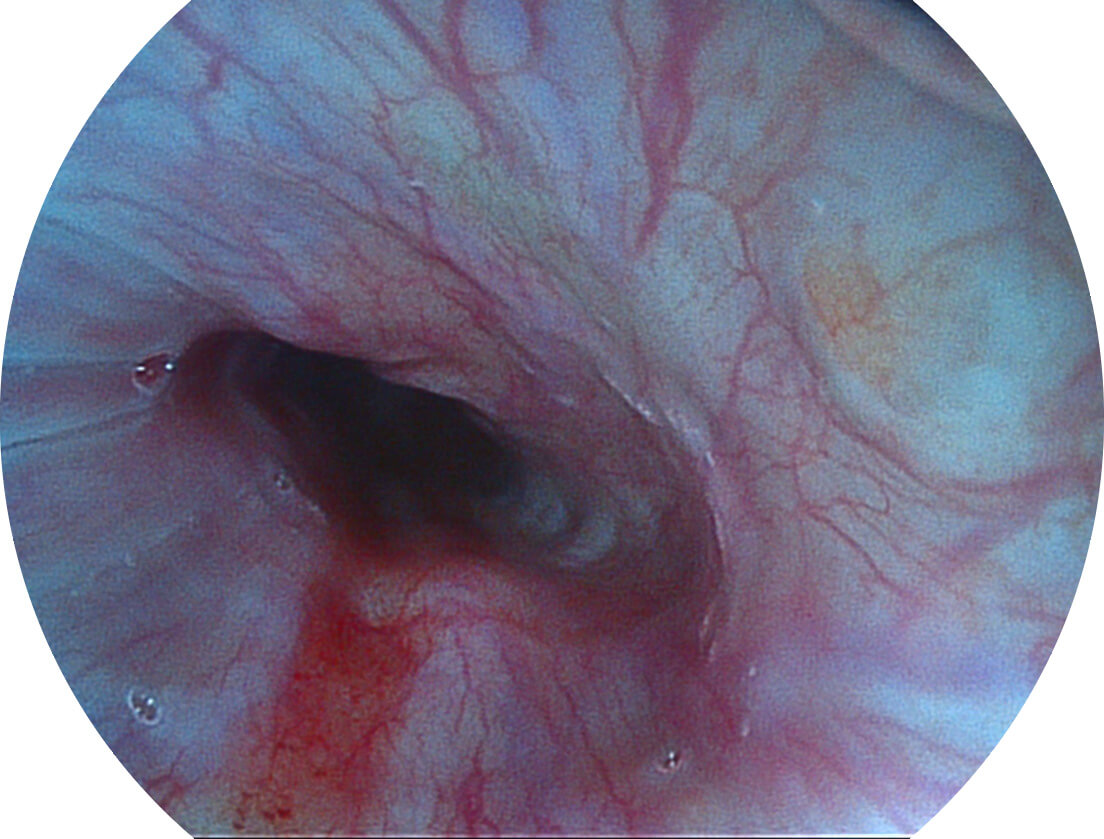

强调浅层黏膜结构的同时,保证照明亮度和提升浅层微血管与中层血管颜色对比度,病变边界更清晰。

白光图像

VIST图像